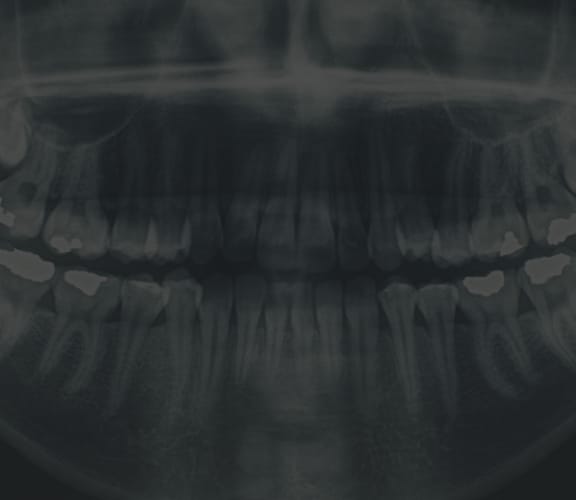

Any of these can exist at birth or may be acquired after birth as a result of hereditary or environmental influences or the result of trauma to the face. Before any treatment begins, a consultation will be held to perform a complete examination with x-rays. During the pre-treatment consultation process, feel free to ask any questions that you have regarding your treatment. When you are fully informed about the aspects of your care, you and your dental team will make the decision to proceed with treatment together.

Our office uses modern computer techniques and three-dimensional models to show you exactly how your surgery will be approached. Using comprehensive facial X-rays and computer video imaging, we can show you how your bite will be improved and even give you an idea of how you'll look after surgery. This helps you understand the surgical process and the extent of the treatment prescribed and to see the benefits of Orthognathic surgery.